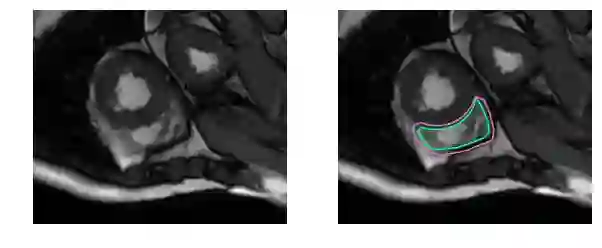

这是一个分割起来很容易的例子。这一个比较困难:

而这对于没有经过训练的眼睛来说完全是一个挑战: